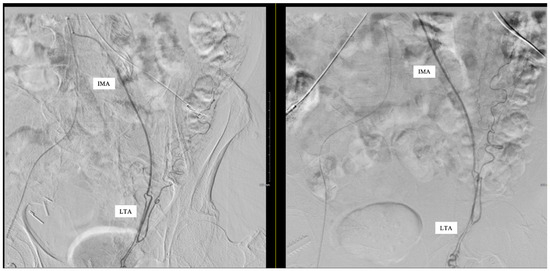

Aberrant Left Testicular Artery Originating from the Inferior Mesenteric Artery Identified on Angiography in a Patient with Gastrointestinal Bleeding: Case Report

| LTA | Left Testicular Artery |

| IMA | Inferior Mesenteric Artery |